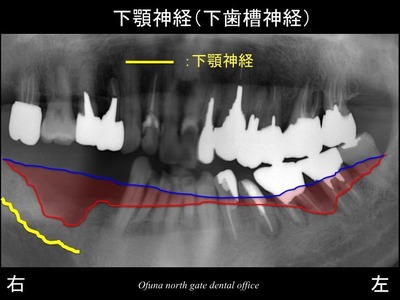

いつものように 骨吸収の状態を分かりやすくするために

骨吸収の状態を線で書いたのが以下のレントゲンになります。

青線が骨吸収を起こす前の骨の位置です。

赤線は、現在の骨の位置です。

かなりの骨吸収が起こっているのが分かるかと思います。

さらに わかりやすくするために、

骨吸収部位を赤色で表示します。

右側では著しい骨吸収が起こっているのが分かります。

さらにまだ他の問題もありました。

下顎神経(下歯槽神経)の存在です。

下顎神経は、下顎の歯の下方に存在する太い神経の管のことです。

この神経の管の位置には個人差があります。

比較的下方にある方もいらっしゃれば、

上方(歯に近い部分)に存在している場合もあります。

この患者様の場合、

下顎神経は、歯に近い部分(上の方)に存在していました。

また、骨吸収が大きいことも問題でした。

こうしたことがあり 残っている骨量は少なく、

インプラントを埋め込むための骨の高さは 非常に少ない状態でした。